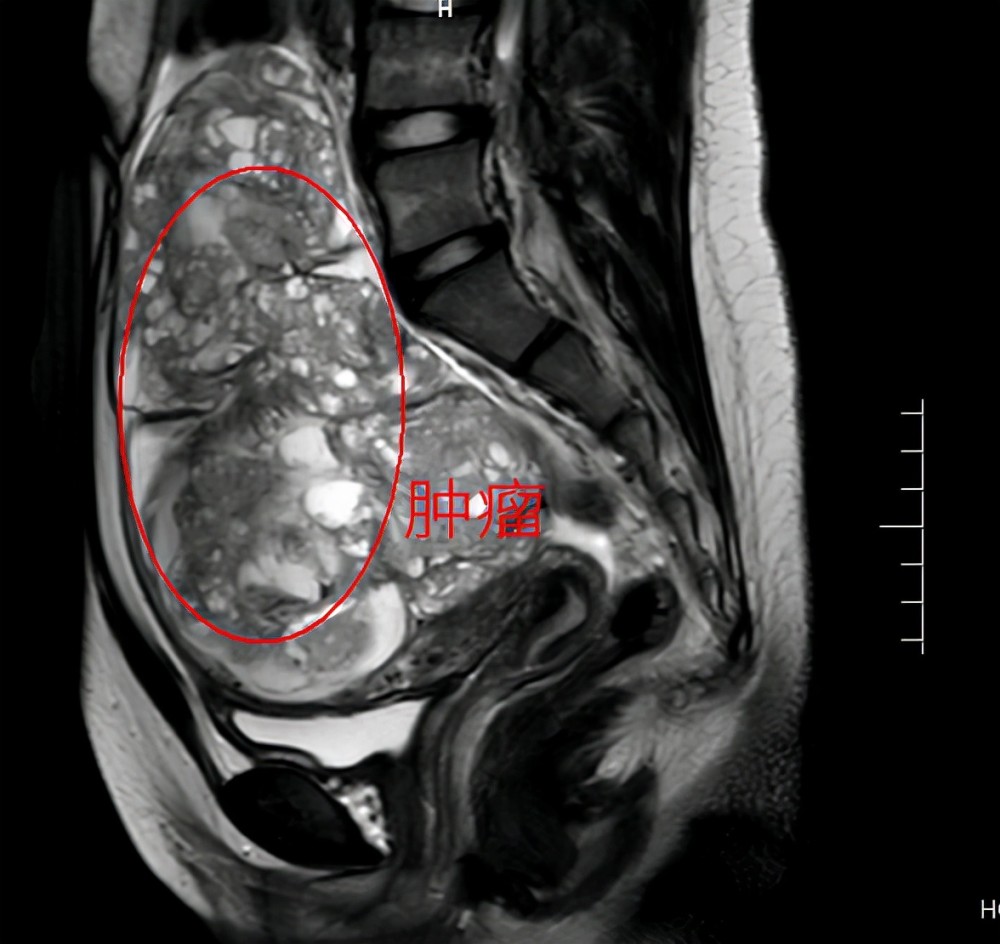

恶性畸胎瘤

内胚窦瘤?恶性畸胎瘤?